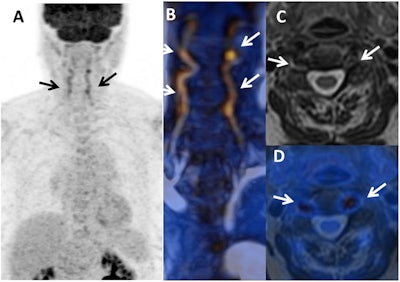

PET and MR images show the initial diagnosis of giant cell arteritis (GCA) in a female with temporal headaches and acute-phase proteins that can cause inflammation but no vascular signs or join pain (arthralgia). There is an inflammatory pattern with clear FDG uptake in vertebral arteries in maximum intensity projection (A) and fusion MR angiography/PET (B) (arrows), which is associated with arterial wall thickening on axial T2-weighted MR image (C) and T2-weighted/PET fusion (D). Images courtesy of Scientific Reports.Clinical benefits